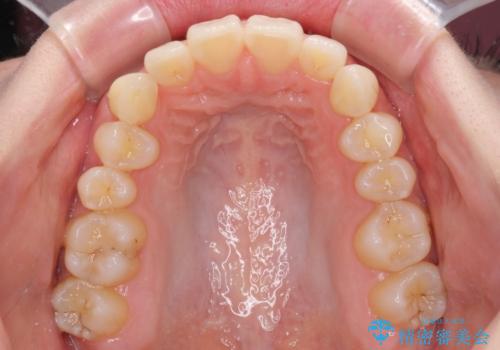

狭い上顎骨を拡大 急速拡大装置を併用したインビザライン矯正

- 前歯のクロスバイトや残存している乳歯を気にして来院された患者様です。

上顎骨の幅が下顎骨よりも小さいので、拡大装置により骨幅を広げて上下関係を改善し、その後インビザラインにて歯並びを整えることとしました。

上下の骨幅を改善したことで、スムーズに歯列矯正を行うことができました。